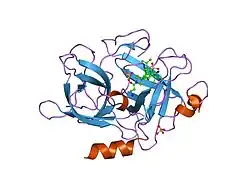

Urokinase is a 411-residue protein, consisting of three domains: the serine protease domain (consisting of residues 159–411), the kringle domain (consisting of residues 50-131), and the EGF-like domain (consisting of residues 1-49). The kringle domain and the serine protease domain are connected by an interdomain linker or connecting peptide (consisting of residues 132–158). Urokinase is synthesized as a zymogen form (prourokinase or single-chain urokinase), and is activated by proteolytic cleavage between Lys158 and Ile159. The two resulting chains are kept together by a disulfide bond between Cys148 and Cys279.[9]